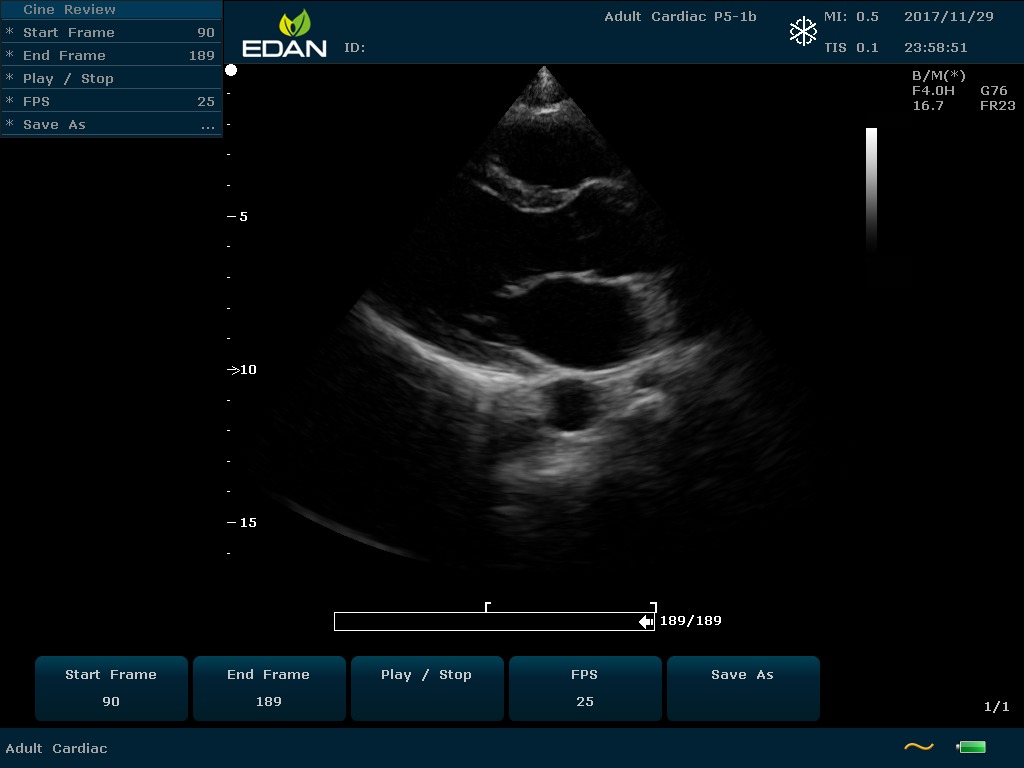

Особенность U60 Edan — расширенное применение. Ультразвуковой аппарат рекомендован для абдоминальных исследований, гинекологии и акушерства, кардиологии, педиатрии, урологии, изучения малых органов, сосудов. Для U60 Edan используются конвексные, линейные, фазированные и внутриполостные датчики.

Передовые технологии позволяют повысить качество визуализации в несколько раз. УЗИ-аппарат U60 Edan отличается возможностью быстрой настройки визуализации. Специальные функции позволяют моментально отображать данные за счет быстрой оптимизации параметров. Режимы визуализации: B-mode, M-mode, Color Doppler, Power Doppler Imaging, Pulsed Wave Doppler, Continuous Doppler.